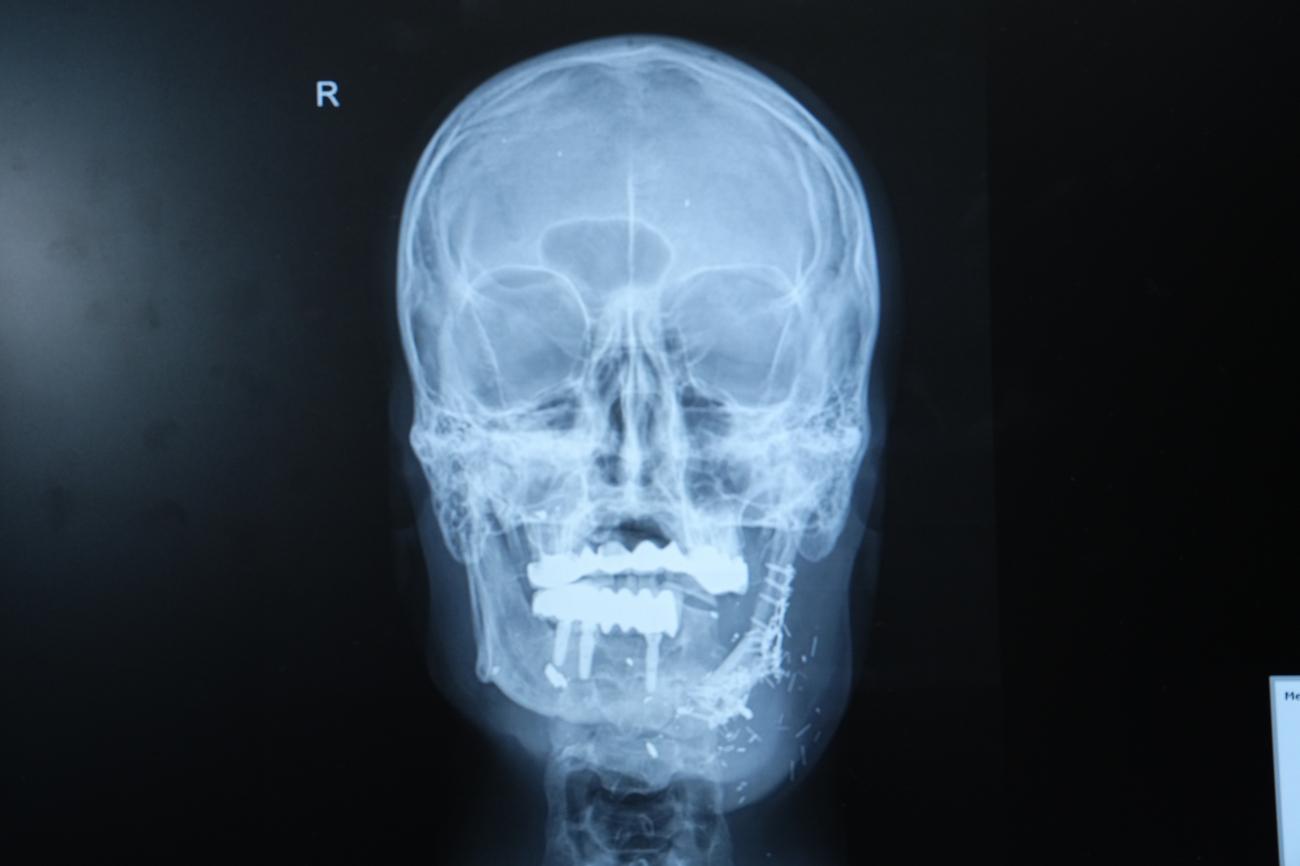

Hastanın durumunun epey komplike olduğunu lisana getiren Doç. Dr. Özkan, “Hastamız ateşli silah yaralanması sonrası çenesinin yarısını kaybetmişti. Daha evvel farklı merkezlerde ameliyat olmuş ancak nakiller başarısız olmuştu. Hem çene bütünlüğünü sağlamak hem de ileride implant yapılabilecek sağlam bir kemik dokusu oluşturmak gerekiyordu. Hastanın bacağından aldığımız kemiği mikrocerrahi sistemle çeneye naklettik. Damarlara ilişki yaptık, plaklarla sabitledik. Bu sayede hem işlevsel hem de estetik olarak başarılı bir sonuç elde ettik” diye konuştu.

Doç. Dr. Özkan, bu tür olaylarda mikrocerrahinin kıymetine dikkat çekerek, “Kompozit doku eksikliklerinde vasküler kemik transferi bize büyük avantaj sağlıyor. Hastamız şu an kendi beslenmesini sağlayabiliyor. Önümüzdeki süreçte kemik düzgünleşmesini tamamladıktan sonra diş implantları yerleştireceğiz ve hastamız çok daha rahat beslenebilecek.” biçiminde konuştu.